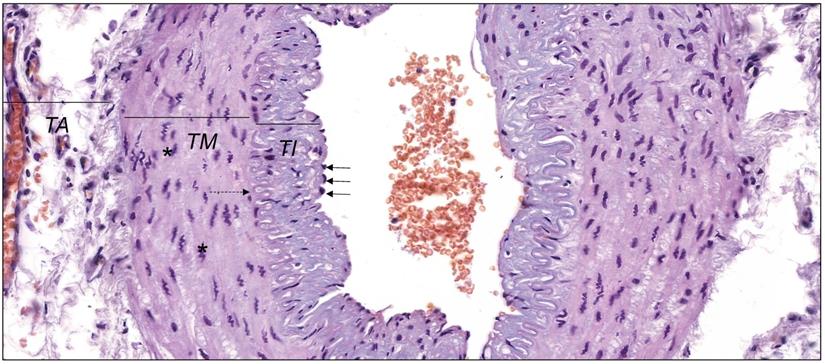

In the physiological conditions, endothelial cells and smooth muscle cells control release of MMPs and TIMPs on the constant level. It enables to keep the balance between degradation and synthesis of the blood vessel wall elements. The histological structure of the wall of muscular artery was presented in Figure 1. Each type of endothelium damage results in the activation of the inflammatory cascade and the adhesion of the monocytes and macrophages to the vessel wall results in the violation of stability and the uncontrolled increase of MMPs activity [31, 39, 40]. Additionally, the activity of endopeptidases is strengthened by constant growth of the proinflammatory cytokines, tumor necrosis factors or oxidized lipoproteins with low density. The activity of metalloproteinases itself is based on setting the path for the inflammatory cells, destruction of the extracellular matrix proteins as well as stimulation and proliferation of smooth muscles cells [39, 41].

Figure 1

The wall of muscular artery presenting tunica intima (TI) lined with endothelium with nuclei of endothelial cells (black arrows), tunica media (TM) with nuclei of vascular smooth muscle cells (* ) and tunica adventitia (TA). Between TI and TM internal elastic lamina is visible (dashed arrow). Hematoxylin and eosin staining (objective magnification, ×40). Original photography by Aleksandra Wilk, Department of Histology and Embryology, Pomeranian Medical University in Szczecin, Poland.